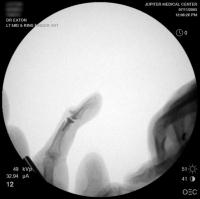

Intraoperative fluoroscopy using the same technique as above. The trial spacers:

The final implant: